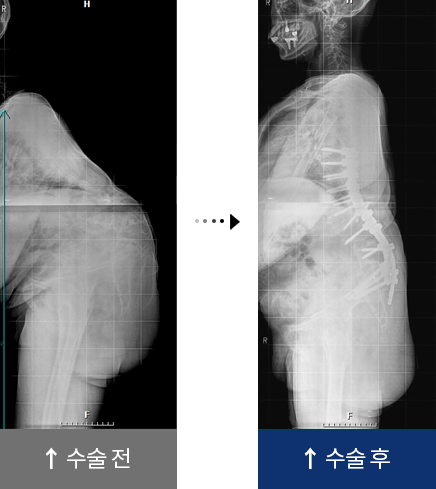

결핵성 후만증